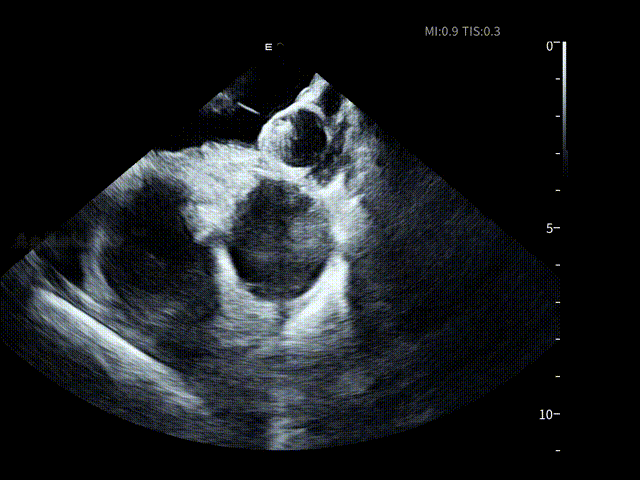

通过ICE的多角度实时成像,术者在左房内近距离观察左心耳的开口形态、分叶数结构及周围解剖关系,并对潜在血栓进行动态筛查,并选择合适的封堵器型号选择并制定释放策略。

90°观察LAA

90°观察封堵器

90°送猪尾导丝进LAA